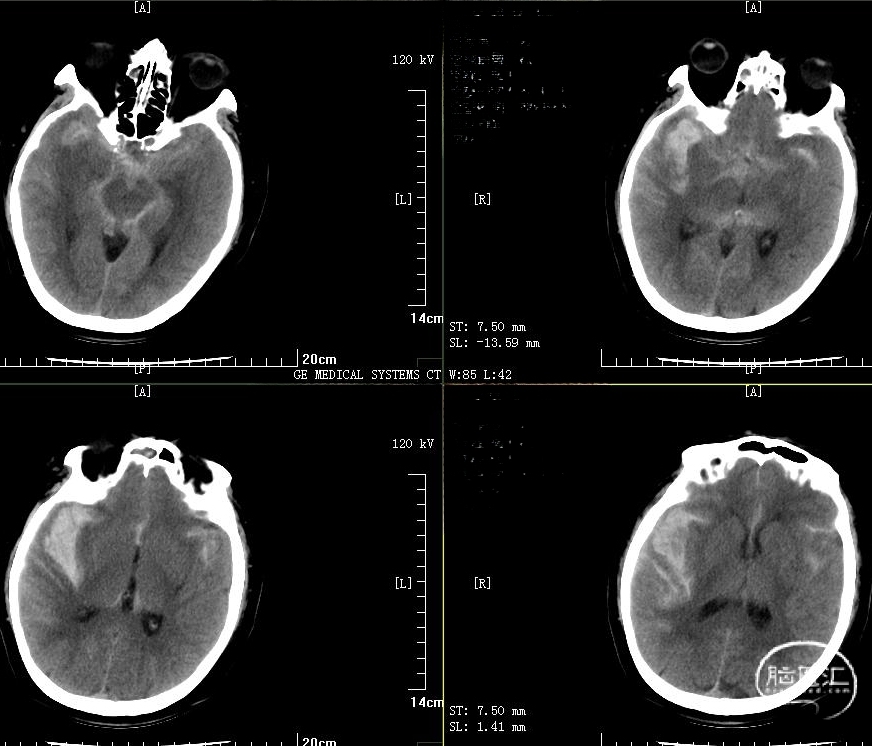

术前头颅CT

入科后患者意识呈嗜睡状,格拉斯哥评分11分;急诊行脑血管造影提示:右侧大脑中动脉动脉瘤。

2、合并右侧颞叶脑内血肿,量约30ml;